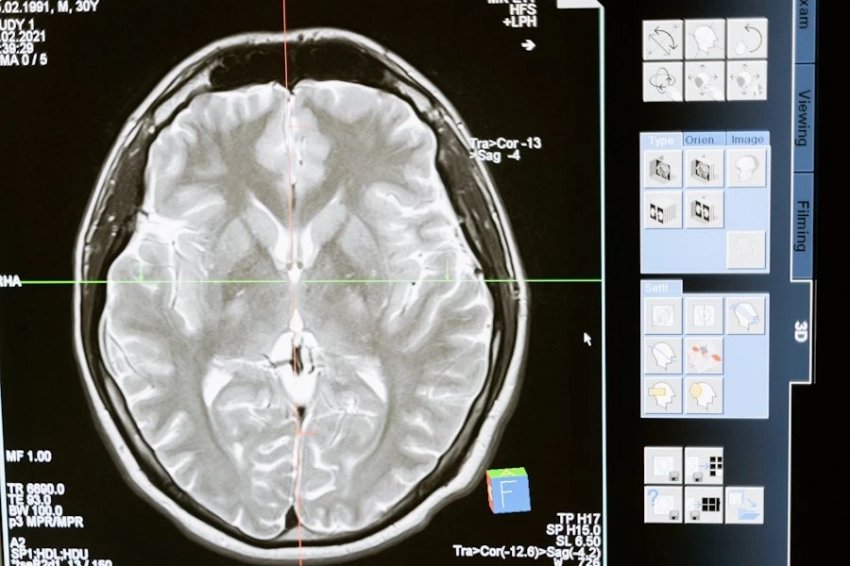

Daily Mail: врачи назвали главные факторы, что помогают защититься от деменции

Доктора дали ряд рекомендаций, какие действия способствуют снижению рисков деменции.